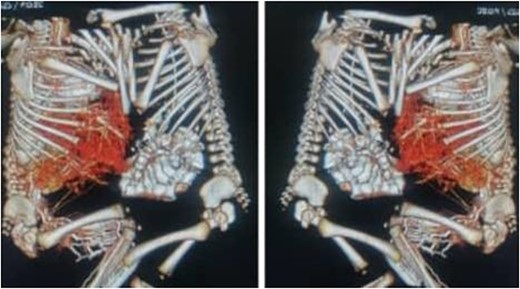

The mother was a 21-year-old female with a family history of multiple pregnancies, para three delivered uneventfully vaginally with a good outcome. Her pregnancy passed well with good antenatal care and early use of tonics, on 30 weeks the abdominal ultrasound revealed monochronic conjoined twins. At 40 weeks gestation, an emergency cesarian section was done due to labor pain, outcome was full-term, monochromic conjoined twins, cephalic, cried immediately and passed urine and meconium within 1st 24 h. On examination, both babies appeared well, not pale or jaundiced and not distressed, and weighed 2.4 kg for each one. They were fused from the xiphoid to the umbilicus with the used area covered by skin, and shared the same umbilical cord. Abdominal Computed tomography revealed a fusion of the liver through a large isthmus side by side with normal liver size and texture, no connections at the portal vein, normal vena cava and other structures (Fig. 1). other organs were entirely normal. Echocardiography showed that one twin has dextrocardia, a small restrictive Ventricular septal defect with a left to right shunt. So, the decision to elective surgical operation was made.

Abdominal computed tomography revealed a fusion of the liver through a large isthmus with normal liver and without vascular connections.